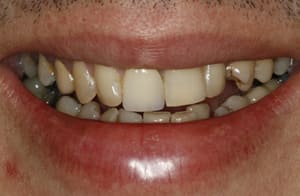

Thank you to our patients that have allowed us to show examples of our work

Have a look at just some of the many patient examples we have captured from BEFORE and AFTER their treatments and cosmetic surgeries.

From Whitening to Veneers, Fillings to Cosmetic Teeth Makeovers, here are some examples of the work that Dr. Dadabhai has provided to his patients to give them a more confident smile and a positive, pain free feeling.

Much of the work we carry out is to relieve pain and of course maintain the health of your teeth and gums, but many of our patients now ask for Cosmetic work to give them a more confident smile.

Cosmetic support has improved hugely over the last few years. Book a Consultation with Dr Dadabhai and he will prescribe a course of treatment to complete your perfect SMILE transformation.